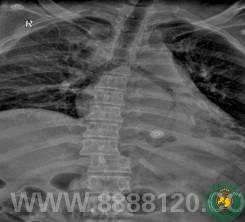

360°减压复位融合技术创造手术辉煌

360°减压复位融合技术创造手术辉煌6494

宜宾市第二人民医院 图文